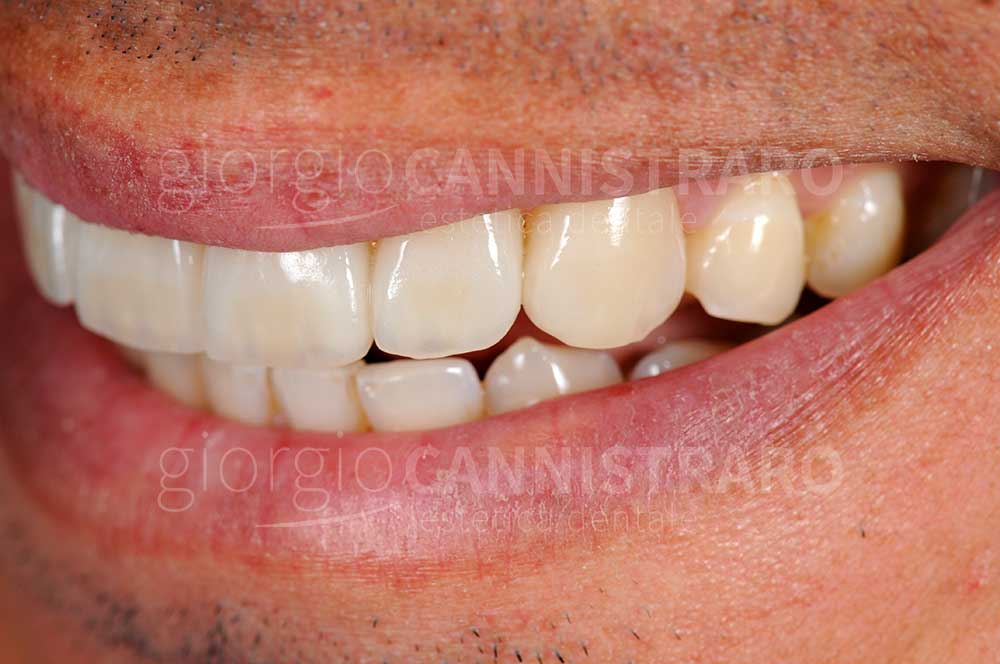

Casi di faccette in ceramica

Faccette in ceramica settore antero-superiore per eccessivo spazio tra i denti

Ragazzo 30 anni